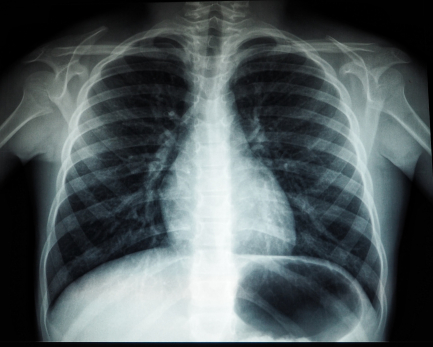

Медики назвали первые симптомы рака легкого, который занимает первое место в структуре заболеваемости и смертности среди всех онкологических заболеваний.

На ранних стадиях он протекает бессимптомно, но человека должен обязательно насторожить кашель, особенно с кровяными выделениями. Кроме того, на ранних стадиях больной страдает одышкой, болями в грудной клетке, возможна осиплость голоса, беспричинная потеря веса и общее недомогание - повышение температуры, слабость, быстрая утомляемость.

- Чем раньше будет выявлен рак легкого, тем больше шансов его вылечить. Если затягивать с визитом к врачу и не начать лечение на ранних стадиях, злокачественный процесс может распространиться за пределы органа, цитирует РГ слова гендиректора НМИЦ онкологии Минздрава Олега Кита.

Врачи напоминают, что 90 процентов больных раком легких - это курильщики. В группе риска также работники вредных производств. Необходимо повышенное внимание к своему здоровью также пациентам после вирусных инфекций, с наличием фоновых заболеваний, при наличии рака легкого у родственников.